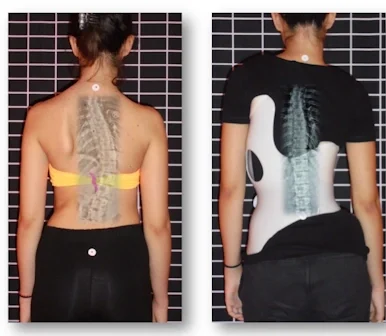

الضغط الصحيح لحزام اعوجاج العمود الفقري: الضلع أم الفقرة؟ عندما يُشخَّص الطفل أو المراهق بوجود اعوجاج في العمود الفقري، يبدأ الأهل في البحث عن أفضل طرق العلاج غير الجراحي. ويعد حزام اعوجاج العمود الفقري

ضغط حزام اعوجاج العمود الفقري : كيف يؤثر على العضلات والعظام والأقراص بين الفقرات؟ يعاني بعض الأطفال والمراهقين من اعوجاج العمود الفقري مجهول السبب عند المراهقين، وهي حالة يحدث فيها انحناء غير طبيعي في

مؤشر جديد يتنبئ بتطور الأنحناء مع حزام اعوجاج العمود الفقري عند المراهقين بسهولة يعاني بعض الأطفال والمراهقين من اعوجاج العمود الفقري مجهول السبب، وهي حالة يحدث فيها انحناء جانبي غير طبيعي في العمود الفقري